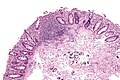

Lymph node

LN features:[8]

- Reactive germinal centers (pale areas - larger than usual).

- Often poorly demarcated - due to loose epithelioid cell clusters at germinal center edge - key feature.

- Epithelioid cells - perifollicular & intrafollicular.

- Loose aggregates of histiocytes (do not form round granulomas):

- Abundant pale cytoplasm.

- Nucleoli.

- Monocytoid cells (monocyte-like cells) - in cortex & paracortex.

- Large cells in islands/sheets key feature with:

- Abundant pale cytoplasm - important.

- Well-defined cell border - important.

- Singular nucleus.

- Cell clusters usually have interspersed neutrophils.